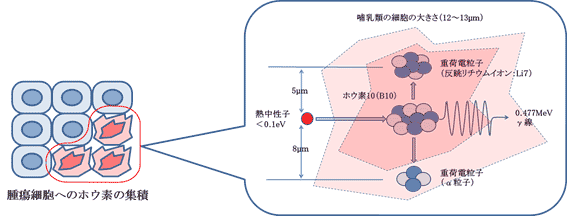

- 精 总缓解率达69%!硼中子疗法成为对抗癌细胞的“秘密武器”

- 精 肿瘤缩小86%!关于硼中子疗法你了解多少?

- 精 前锋:硼中子俘获治疗(BNCT)为肿瘤患者带来福音